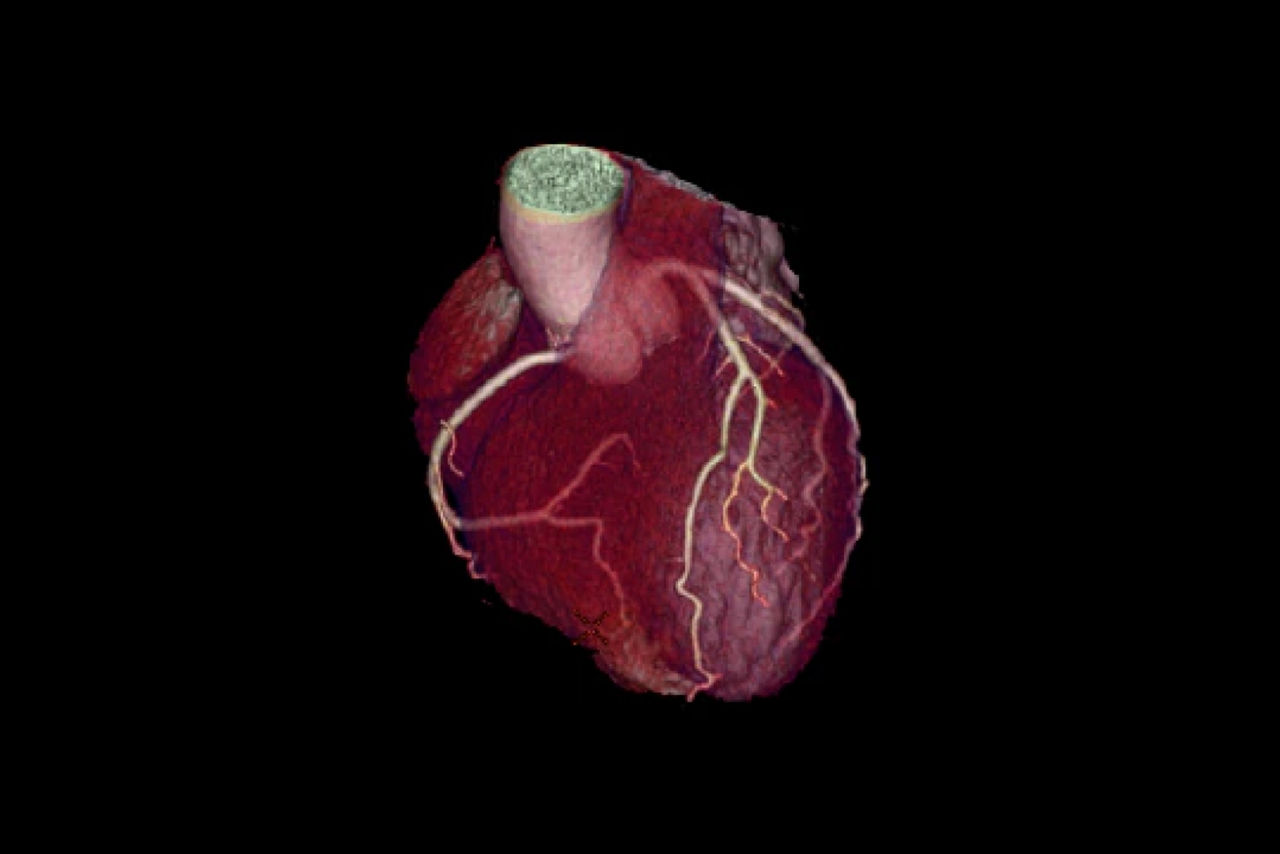

Post-scan

Cardiac post-processing features

SnapShot Freeze 2 provides an automated whole-heart motion-correction algorithm with an effective temporal resolution of 29 ms*.

Automated post-processing applications for coronary analysis and calcium score allow you to read images directly on your console or secondary image reading station.